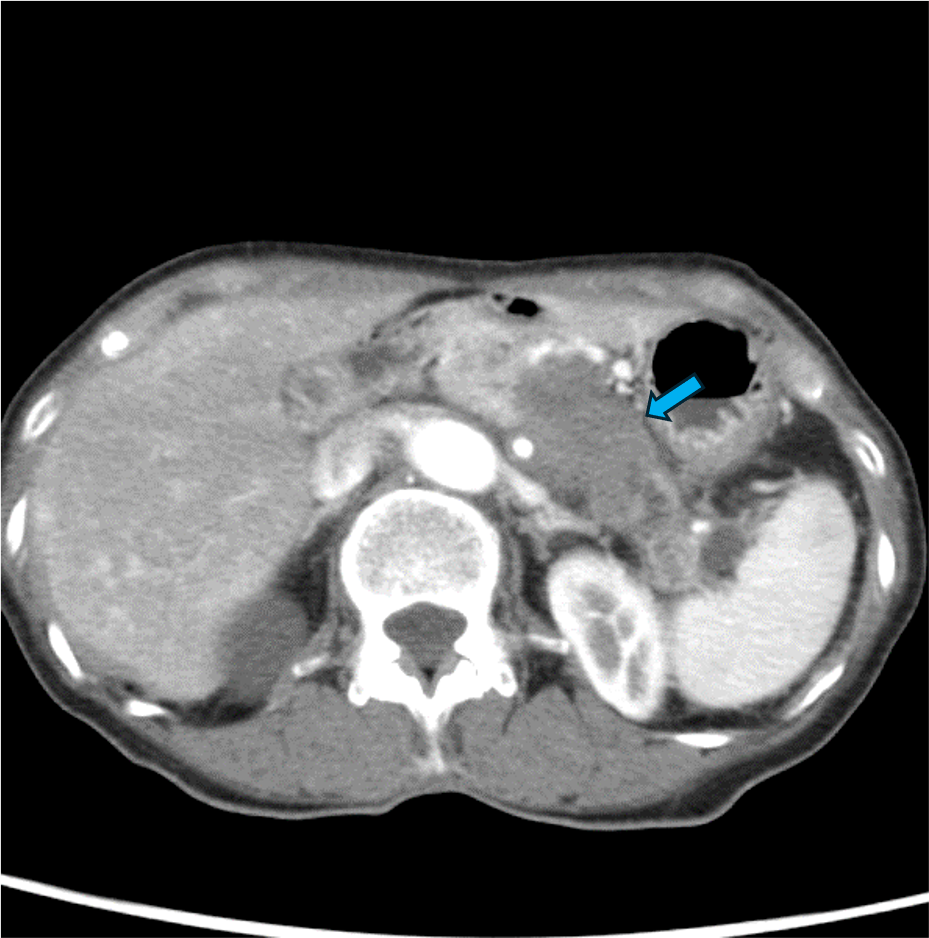

60歳台女性。心窩部痛と背部痛を主訴に来院。内視鏡を施行したところ、胃食道静脈瘤を認めたため内視鏡的静脈瘤結紮術を実施した。しかし、その後も背部痛は継続し、体重減少も出現した。腫瘍マーカーCA19-9、DUPAN-2の高値も認めたため悪性腫瘍精査目的にDynamic CTが撮影された。CTにて膵尾部腫瘍が認められた。腫瘍は腹腔動脈(CeA)、上腸間膜動脈(SMA)、門脈本幹(PV)、上腸間膜静脈(SMV)に浸潤を認めた。CTにてUnresectableと診断され、化学療法が施行された。

通常型膵癌はdesmoplastic反応すなわち間質の線維化が強く、周囲の組織を巻き込みながら成長する。また一般的に阻血に抵抗性で腫瘍内出血や壊死、脂肪変性は起こしにくい。Dynamic CTでは乏血性で浸潤性増殖を呈する腫瘍として描出され、他の膵腫瘍の鑑別に有用である。CTは、腫瘍の大きさ、周囲組織への浸潤、リンパ節転移、遠隔転移の有無などを評価できるため、腫瘍の進展度を正確に診断し、適切な治療方針を決定するための重要な情報が得られる。特に、局所における切除の可否の決定に動脈系と門脈系への浸潤の有無を評価することが重要である。膵癌取扱い規約(JPS)第7版ではUnresectable、borderline resectableに関する事項が追加され、CT診断において記載すべき重要な項目である。

本検査は食道静脈瘤が認められたことから、肝臓プロトコルによる撮像を行っている。膵臓をターゲットとするのであれば、動脈相よりタイミングをもう少し遅らせた膵実質相を撮像するべきである。また、ECVを評価する際は、十分造影剤が間質に到達した時相が好ましく、本検査で施行した180秒後の平衡相の撮像は、早すぎると予想される。